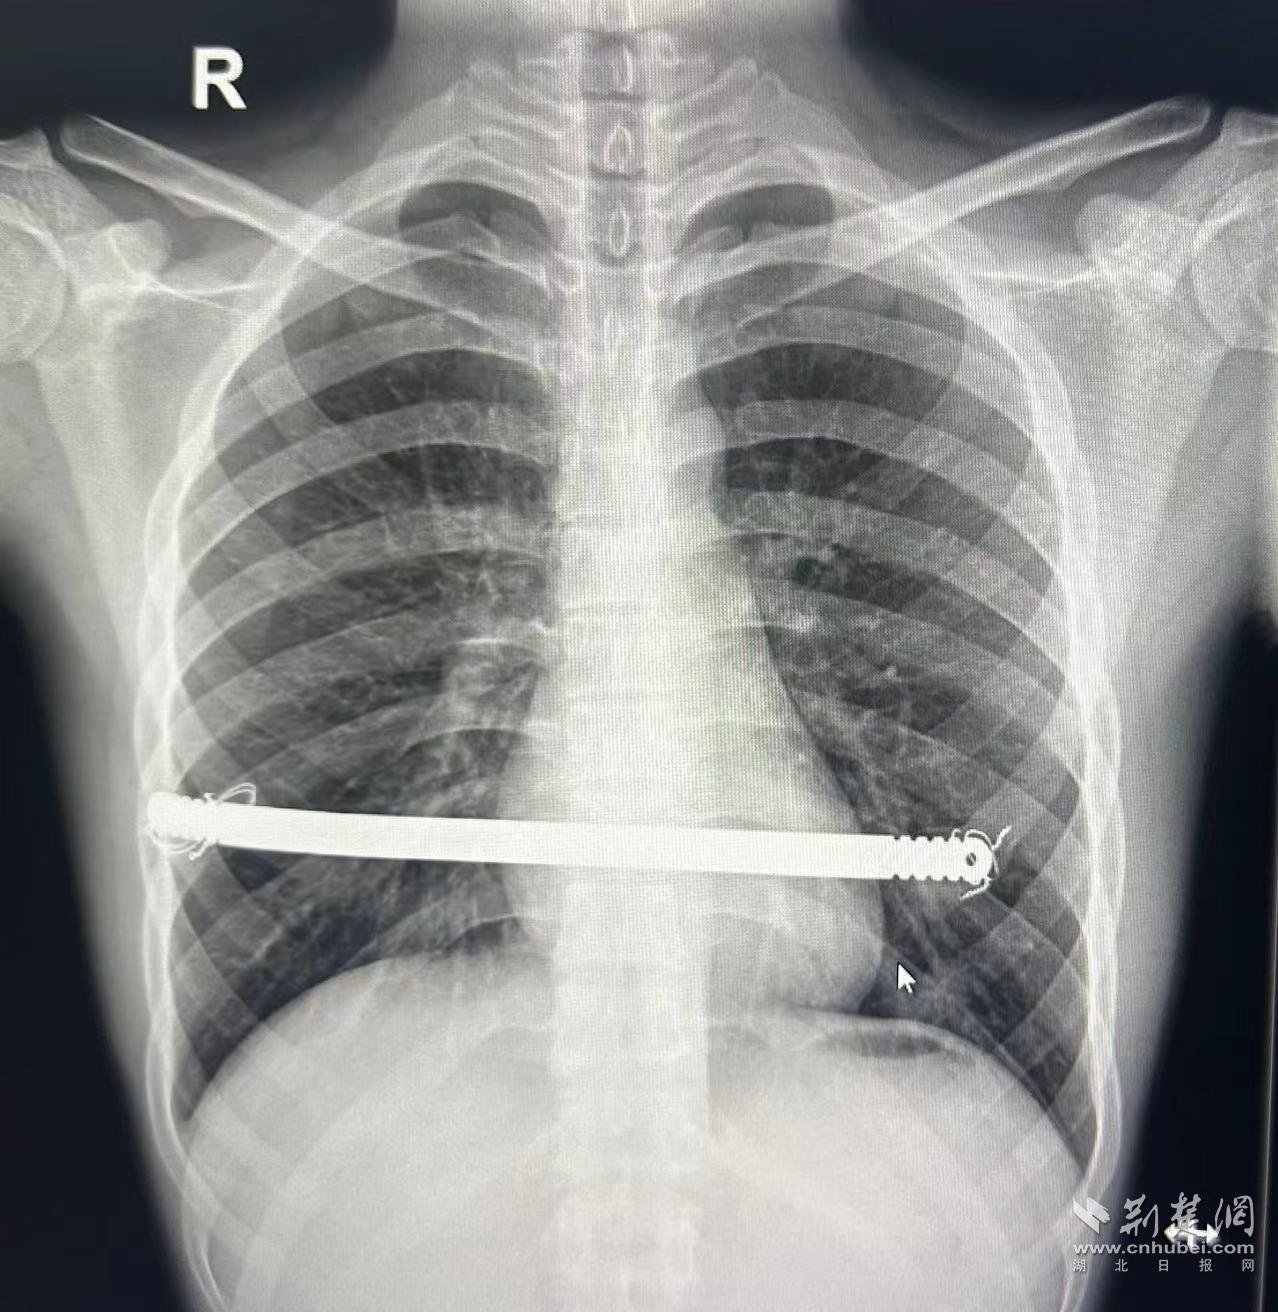

7月21日,手術精準展開。團隊僅在欣欣第6肋間兩側切開約2cm小口,在胸腔鏡引導下,將一條寬1.27cm精心塑形的鋼板巧妙地穿到凹陷胸骨的后方,像架起一座微型的“拱橋”,塌陷的胸壁瞬間被穩穩托起。全程僅耗時30分鐘,欣欣胸廓外觀立刻恢復如常。

術前和術后胸廓對比。